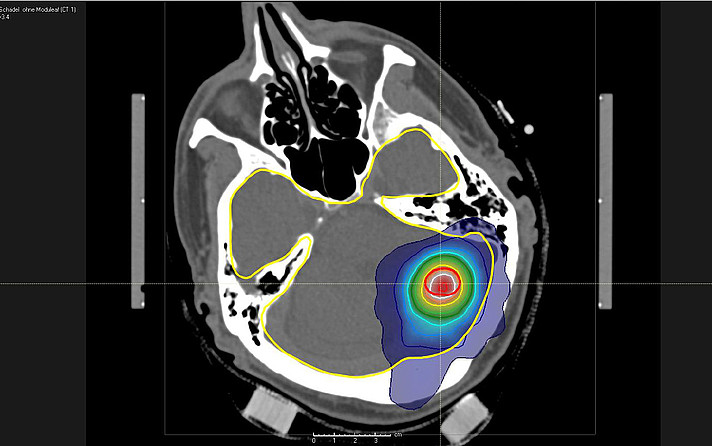

Neben wissenschaftlichen Präsentationen wurde den Studierenden auch eine Führung durch die Abteilung geboten, wodurch ein guter Einblick in die Arbeit in dieser hochmodernen Abteilung gewonnen werden konnte. Das Glanzstück der Abteilung ist mit Sicherheit ein Gammaknife © der modernsten Bauart. Hierbei handelt es sich um ein hochpräzises Bestrahlungsgerät, welche es ermöglicht die Strahlung von über 200 einzelnen radioaktiven Quellen in einem einzelnen Punkt zu bündeln. Dadurch ist es möglich, die Strahlenbelastung für das umliegende, gesunde Gewebe zu minimieren. Anwendung findet die Methode v.a. bei Tumoren oder Gefäßmissbildungen im Gehirn.